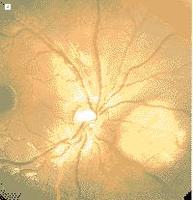

3.眼底螢光血管造影 早期可以見到典型的境界清楚的迴旋形萎縮區,萎縮區內脈絡膜大血管清晰可見,有時早期萎縮斑外緣的色素上皮透明,並從此處可見到脈絡膜血管。螢光染料向血管周圍滲漏,滲漏區域比檢眼鏡所見病變的範圍大,說明色素上皮有廣泛性損害(圖1B)。晚期脈絡膜全層萎縮後,出現鞏膜強螢光。